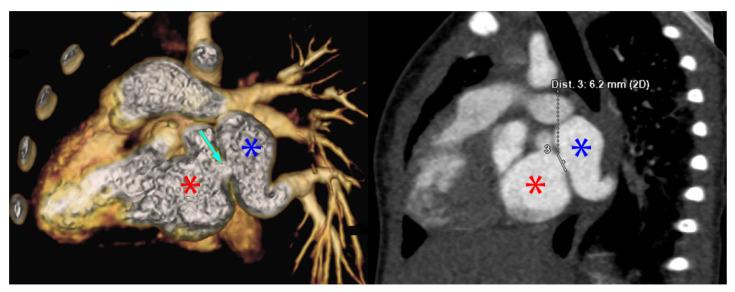

Pulmonary vein stenosis (PVS) is a rare, but high mortality and resource intensive disease caused by mechanical obstruction or intraluminal myofibroproliferation, which can be post-surgical or idiopathic. There are increasing options for management including medications, cardiac catheterization procedures, and surgery. We queried the International Quality Improvement Collaborative for Congenital Heart Disease (IQIC) database for cases of PVS and described the cohort including additional congenital lesions and surgeries as well as infectious and mortality outcomes. IQIC is a quality improvement project in low-middle-income countries with the goal of reducing mortality after congenital heart surgery. Three cases were described in detail with relevant images. We identified 57 cases of PVS surgery, with similar mortality to higher income countries. PVS should be recognized as a global disease. More research and collaboration are needed to understand the disease, treatments, and outcomes, and to devise treatment approaches for low resource environments.

肺静脉狭窄(PVS)是一种罕见但死亡率高且资源消耗大的疾病,由机械性梗阻或腔内肌纤维增生引起,可继发于手术或为特发性。治疗选择越来越多,包括药物治疗、心导管介入手术和外科手术。我们查询了国际先天性心脏病质量改进协作组织(IQIC)数据库中的PVS病例,并描述了该队列,包括其他先天性病变和手术以及感染和死亡结局。IQIC是一个中低收入国家的质量改进项目,目标是降低先天性心脏病手术后的死亡率。详细描述了3例病例并配有相关图像。我们确定了57例PVS手术病例,其死亡率与高收入国家相似。PVS应被视为一种全球性疾病。需要更多的研究和合作来了解该疾病、治疗方法和结局,并为资源匮乏地区设计治疗方案。